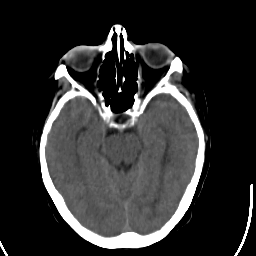

Stroke CT #1 -- Slice #9

[Home][Help][Clinical] Slice 9